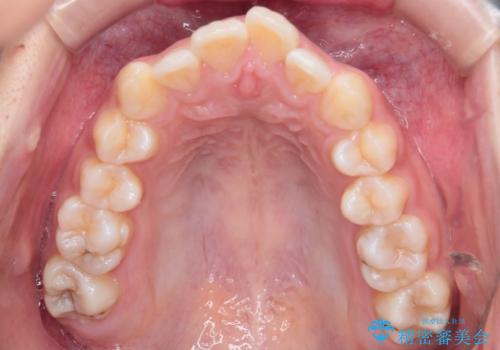

重度の歯のがたつきを、目立たない矯正と抜歯で根本改善

- 前歯から奥歯にかけて歯の重なりが激しい歯のがたつき(重度叢生)を主訴にご来院されました。精密検査の結果、歯が並ぶスペースが大幅に不足しており、歯並びを整え、口元を美しく引っ込めるためには、スペースの確保が必要と診断しました。そこで、上下左右の第一小臼歯(4番目の歯)を計4本抜歯し、そのスペースを利用して歯並び全体を整える抜歯矯正の治療計画を立案。装置には、透明で目立たないインビザラインを採用し、審美性と治療効果の両立を目指しました。

今回の治療では、重度の叢生を改善するため、まず計画通り上下左右4本の小臼歯を抜歯し、歯を並べるための十分なスペースを確保しました。装置には透明で取り外し可能なインビザラインを使用。抜歯によってできたスペースを最大限に活用し、マウスピースを定期的に交換しながら、デコボコを解消しつつ、前歯を効果的に後退させました。

治療の結果、長年の悩みであった重度の歯のがたつきが解消され、口元の突出感も改善。機能的にも安定し、審美的にも美しい、理想的な歯並びを獲得していただけました。